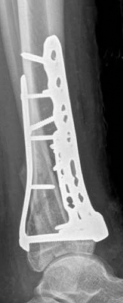

Removal of implants is not mandatory but recommended if implants are prominent under the subcutaneous envelope of the distal tibia. Implant removal should be undertaken only after healing is complete, ie, after 1 year at the earliest. This patient had achieved good radiographic and functional healing at the 1-year postoperative review (Fig 2.2-8 and Fig 2.2-9).

Fig 2.2-8a–b Postoperative x-rays at 1 year showing healed fractures, implants in situ, and limited tibiotalar arthrosis.

1. AP view.

2. Lateral view.